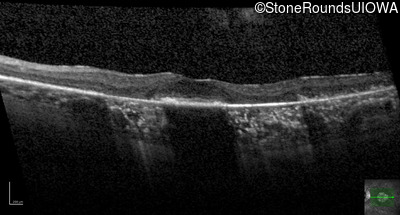

Age at visit: 63 years

This 63 year old woman has had normal vision for most of her life, but recently developed difficulty seeing in dim light.

Diagnosis & molecular findings

AD Retinitis Pigmentosa SAG Cys147Phe TGT>TTT   AD